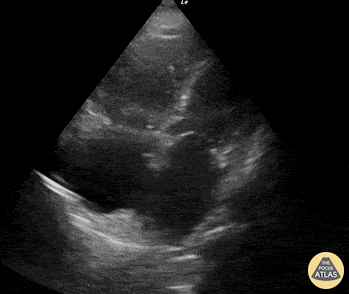

Right Ventricular Dysfunction - McConnell's Sign

An elderly female presented with complete AV heart block. Apical 4-chamber view was performed and was notable for regional RV dysfunction (aka McConnell’s Sign). Though this finding is commonly associated with acute PE, our patient was found to have right coronary artery occlusion as the etiology of all findings. Renato Melo, Emergency Physician at HC de Marília-SP, Brazil. PocusJedi co-founder. @Renato_Melo_